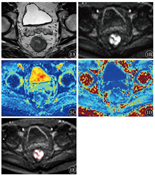

1例直肠癌患者MRI检查结果见图1。2名医师计算ADC、MD及MK的ICC分别为0.934(0.833~0.975)、0.963(0.905~0.981)、0.971(0.949~0.991),2名测量者间一致性良好。

参照MRI确定肿瘤范围,在b值为1 400 s/mm2的DKI连续图像上沿肿瘤轮廓手动勾画感兴趣区(ROI),注意避开坏死、囊变及出血区[12,13,14]。应用Matlab软件(美国MathWorks公司)对图像进行后处理,计算相应的表观扩散系数(ADC)、平均弥散系数(MD)、平均峰度系数(MK),并生成对应参数的伪彩图。采用标准单指数模型计算得出ADC。病灶勾画工作由2名具有8年以上盆腔病灶诊断经验的放射科医师在不知道术后病理结果的情况下完成。